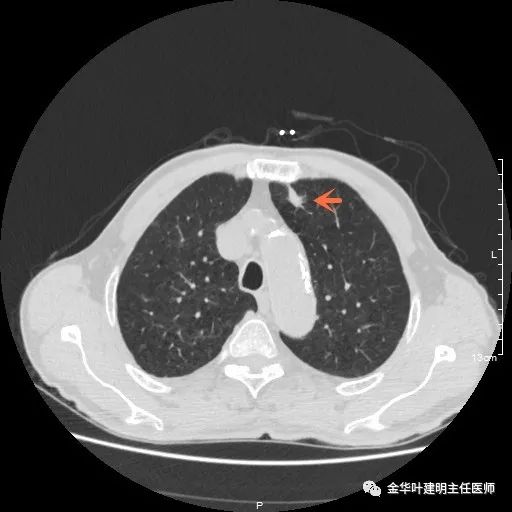

以上示左上叶病灶2。病灶虽然似慢性炎,但有收缩力,有毛刺征,在右侧诸多病灶考虑多原发肺癌的前提下,此灶是恶性的可能性非常大,不能单纯认为其是慢性炎性病灶。就此单灶来看,可以局部切除病检,若示浸润性腺癌,则有肺叶切除的指征。